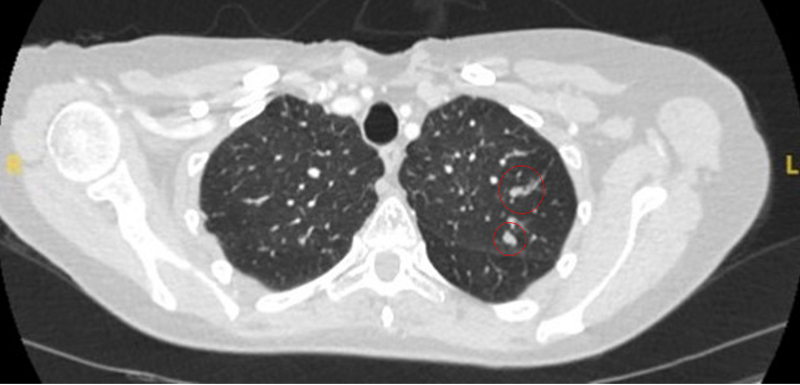

As causas restantes são infrequentes e incluem impactação mucoide, êmbolos sépticos, malformações arteriovenosas e amiloidose pulmonar.

[Figure caption and citation for the preceding image starts]: Tomografia computadorizada (TC) mostrando duas áreas (círculos vermelhos) de impactação mucoide dos brônquios subsegmentares do lobo superior esquerdo, resultando em aparência que mimetiza um nóduloDo acervo de Dr. George Tsaknis, MD, PhD, FRCP (Londres), MRQA, MAcadMEd, PGCert; usado com permissão [Citation ends].